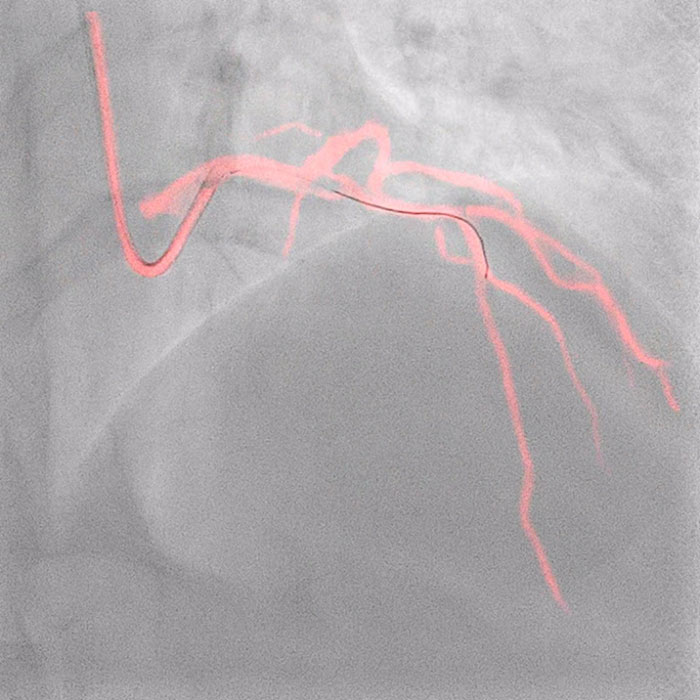

O software Dynamic Coronary Roadmap é uma inovação de visualização em tempo real que elimina a necessidade de injeções adicionais de meio de contraste ao sobrepor o angiograma em imagens fluoroscópicas 2D com compensação de movimento em tempo real para fornecer aos intervencionistas feedback visual contínuo sobre o posicionamento de fios-guia e cateteres. Complementando essa tecnologia, o sistema de orientação de precisão Philips IntraSight agiliza a avaliação de lesões, simplifica o dimensionamento do vaso, permite a entrega precisa do tratamento e também apoia o operador em seu objetivo de reduzir os volumes de contraste.

Philips Dynamic Coronary Roadmap